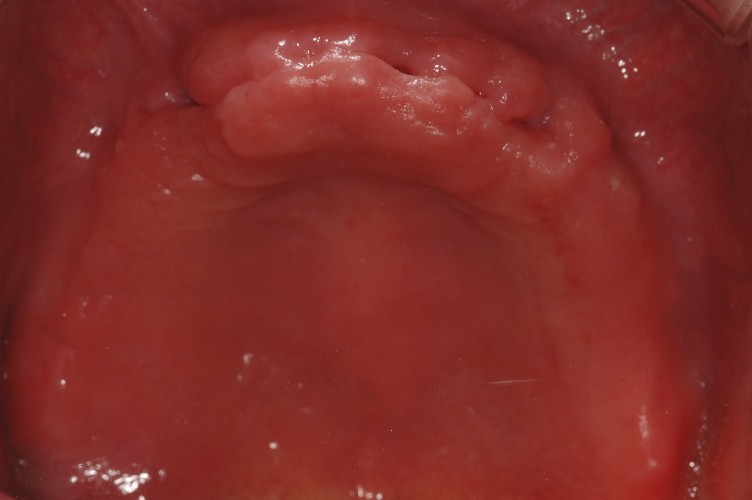

뼈가 좋은부위에서 임플란트시술은 어렵지 않으나, 뼈가 부족해서 뼈이식 혹은 윗니 어금니의 경우 상악동거상술이 필요하거나, 혹은 앞니의 경우 다른 경우보다 보다 섬세한 계획과 시술이 필요합니다.

임플란트는 약 20년전에는 수입임플란트를 많이 하였으나, 최근엔 국내임플란트를 거의 모든 경우에 식립을 하고 덴티스 혹은 오스템임플란트를 사용하고 있으며, 뼈 상태가 약하면 하이드록시 아파타이트가 코팅된 덴티스헵타이트를 사용하고 있습니다.